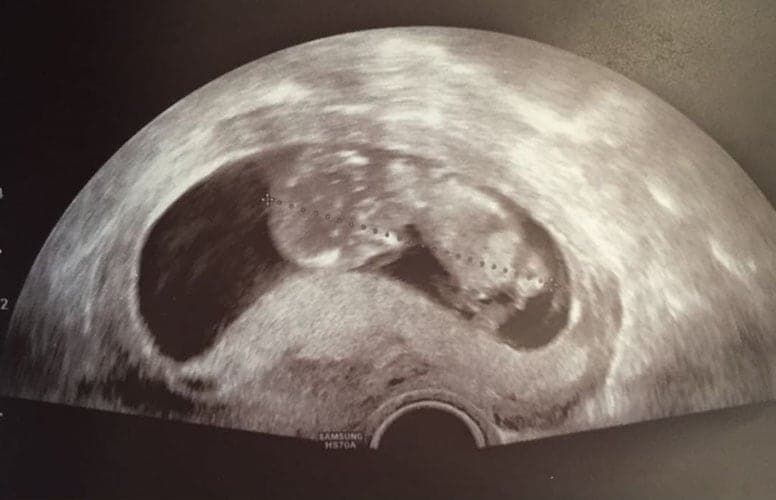

Was kann man auf einem Ultraschallbild erkennen?

Was genau man auf einem Ultraschallbild erkennen kann, hängt nicht nur von der Größe des Babys ab, sondern auch davon wie gut das Ultraschall-Gerät ist, mit dem die Aufnahme gemacht wurde. Auch auf den Ultraschallbildern hier kannst du sehen, dass die Qualität stark schwankt. In der Regel kann man gut den Kopf und RUmpf des Babys erkennen und auch die Gliedmaßen erkennt man selbst als Laie gut.

Wer sich jedoch erhofft Gesichtszüge zu erkennen, der wird oft enttäuscht. Zwar kann man beim 3D-Ultraschall schon eine Menge sehen, aber das umgebende Fruchtwasser sorgt in den allermeisten Fällen für starke Störungen.